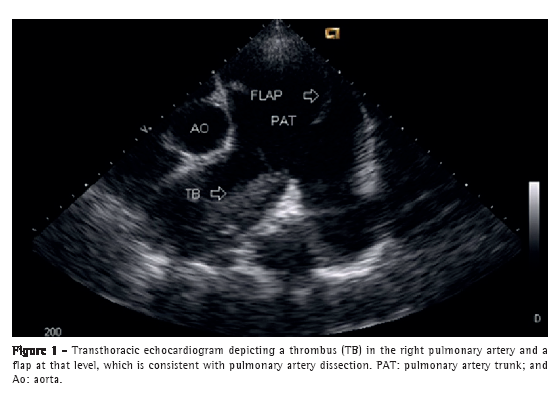

Case reportA 50-year-old male patient diagnosed four years prior with pulmonary hypertension related to schistosomiasis mansoni was admitted to the emergency room of the Federal University of Minas Gerais School of Medicine Hospital das Clínicas, located in the city of Belo Horizonte, Brazil. He presented with new onset, progressively worsening retrosternal chest pain and shortness of breath (functional class III pulmonary hypertension according to the World Health Organization). He had been diagnosed with chronic myeloid leukemia seven months prior and had since been on chemotherapy. At admission, transthoracic echocardiography revealed a large non-obstructive central thrombus in the right main pulmonary artery. The right atrium was dilated, and there was mild tricuspid regurgitation, with an estimated pulmonary artery systolic pressure of 63 mmHg. He was diagnosed as having in situ thrombosis as a complication of the long-standing pulmonary hypertension. After the possibility of acute coronary syndrome had been excluded, he was discharged on warfarin. He was re-admitted two months later due to progressively worsening, refractory chest pain. At that time, he had an SpO2 of 96%, and a third heart sound was audible at the lower left parasternal space, accompanied by a murmur of tricuspid regurgitation. The lungs were clear, and the peripheral arterial pulses were symmetric. Laboratory test results were unremarkable, including serum levels of creatine kinase, creatine kinase MB isoenzyme, and troponin. A resting electrocardiogram showed evidence of acute myocardial ischemia in the anterior leads. Transthoracic Doppler echocardiogram revealed a pulmonary artery systolic pressure of 62 mmHg, a thrombus in the right pulmonary artery, as in the previous examination, and the presence of a flap at that level that was compatible with pulmonary artery dissection (Figure 1). The diagnosis was confirmed by subsequent CT pulmonary angiography (CTPA; Figure 2). He was transferred to another cardiovascular treatment facility, where attempts were made to correct the defect with an endovascular procedure (via the femoral vein). During the perioperative period, the patient presented with refractory cardiogenic shock. Multiple efforts to resuscitate the patient were unsuccessful, and he died in the operating room.